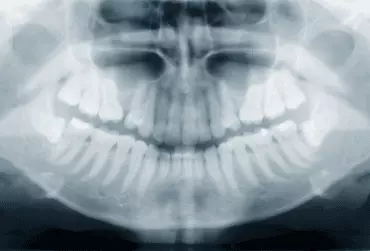

Usunięcie zęba lub zębów w bocznym odcinku kości szczękowych i niezaopatrzenie braków implantami skutkuje w krótkim czasie zanikiem wyrostka zębodołowego oraz pneumatyzacją zatok szczękowych. Podniesienie dna zatoki szczękowej jest obecnie uznaną standardową procedurą implantologiczną. Wykonuje się ją w celu augmentacji wyrostka zębodołowego szczęki. Zabieg ten można wykonać na dwa sposoby. Najczęściej wykorzystywanym sposobem do podniesienia membrany Schneidera jest dojście przez okienko w bocznej ścianie zatoki szczękowej.